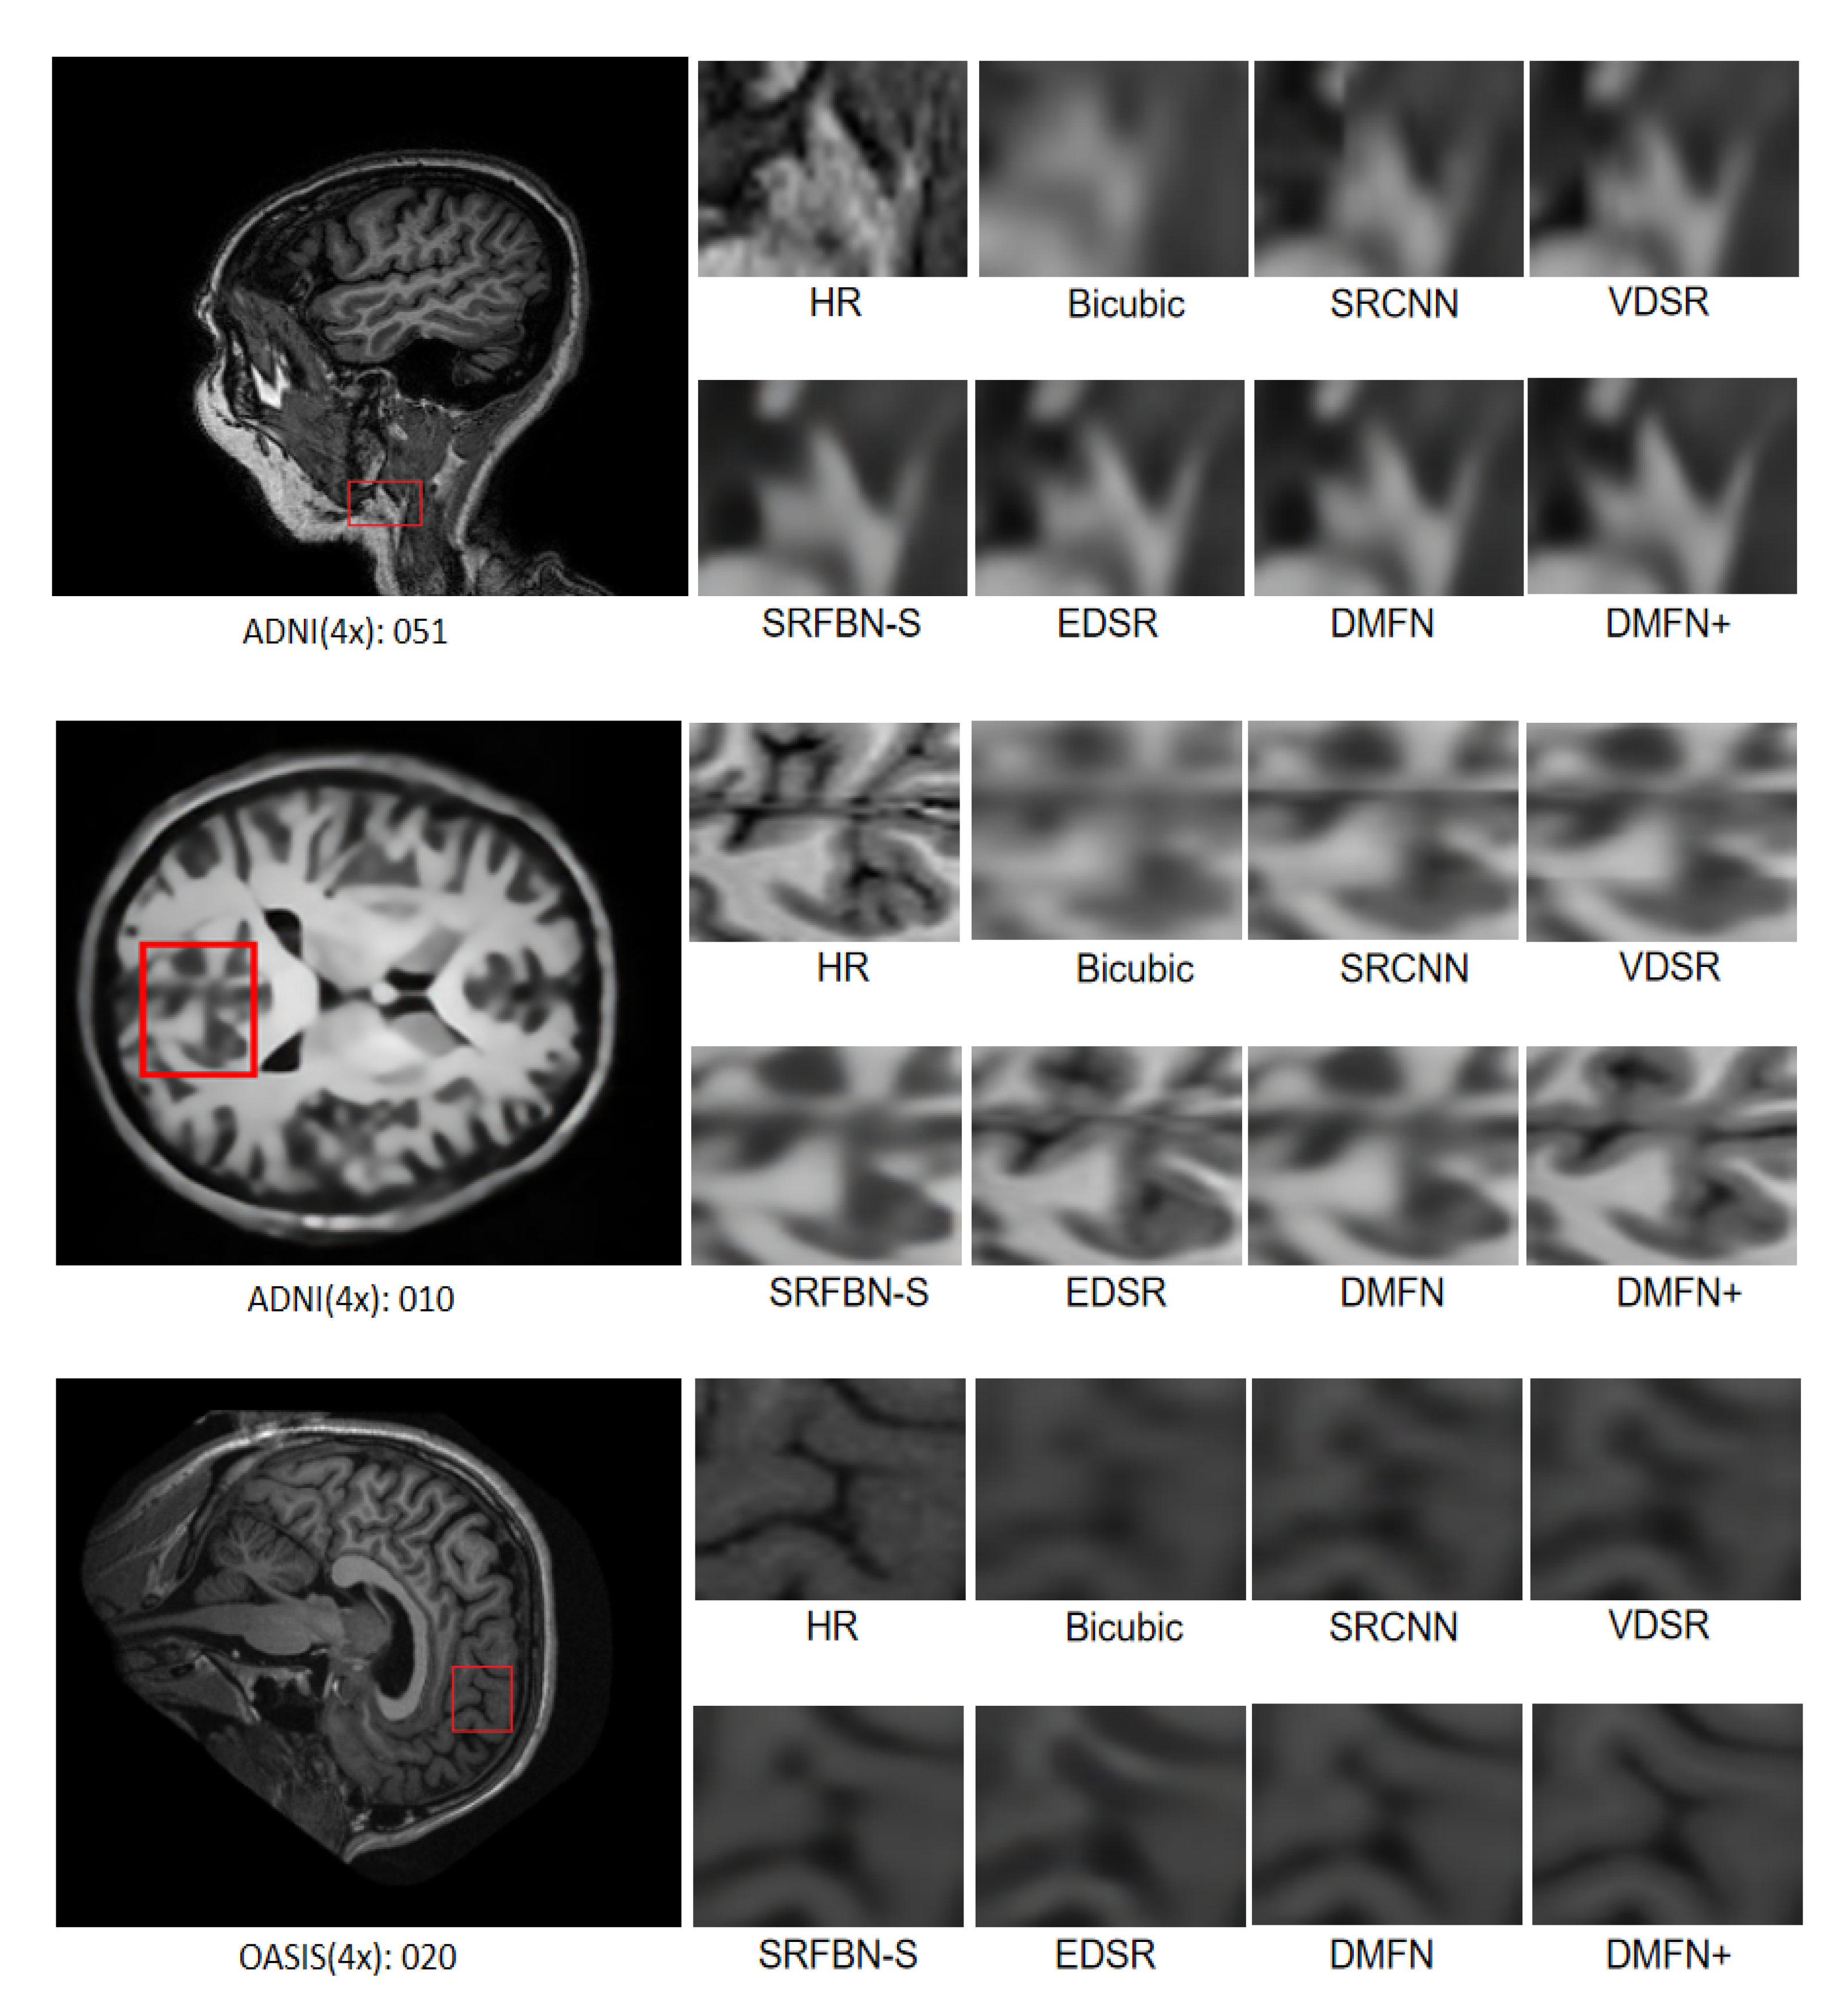

4.7. Comparison with Classical SR Methods

| Methods | Scale | Params | MRI13 | ADNI100 | OASIS100 |

|---|---|---|---|---|---|

| PSNR/SSIM | PSNR/SSIM | PSNR/SSIM | |||

| Bicubic | ×2 | - | 37.95/0.9677 | 30.74/0.8943 | 33.54/0.9585 |

| SRCNN [2] | 8 K | 40.76/0.9820 | 32.49/0.9258 | 35.52/0.9717 | |

| FSRCNN [5] | 13 K | 40.90/0.9809 | 40.90/0.9809 | 34.47/0.7778 | |

| VDSR [8] | 666 K | 41.78/0.9835 | 33.09/0.9328 | 36.70/0.9759 | |

| DRCN [9] | 1774 K | 42.15/0.9838 | 33.22/0.9336 | 37.19/0.9779 | |

| LapSRN [7] | 251 K | 41.99/0.9840 | 32.96/0.9317 | 36.98/0.9772 | |

| SRDenseNet [13] | 7160 K | 42.97/0.9846 | 33.33/0.9348 | 37.69/0.9788 | |

| DDSR [12] | 2020 K | 41.92/0.9833 | 33.00/0.9318 | 36.97/0.9766 | |

| EDSR [14] | 1370 K | 43.61/0.9853 | 33.50/0.9359 | 38.18/0.9797 | |

| SRMD [41] | 1511 K | 42.26/0.9841 | 33.15/0.9335 | 37.27/0.9780 | |

| SRMDNF [41] | 1511 K | 42.76/0.9848 | 33.30/0.9348 | 37.69/0.9794 | |

| SRFBN-S [21] | 282 K | 42.77/0.9843 | 33.29/0.9342 | 38.88/0.9806 | |

| FAWDN [22] | 7170 K | 43.35/0.9850 | 33.41/0.9352 | 37.91/0.9791 | |

| FAWDN+ [22] | 7170 K | 43.59/0.9851 | 33.87/0.9400 | 38.10/0.9798 | |

| DMFN(ours) | 475 K | 43.38/0.9850 | 33.41/0.9353 | 39.27/0.9813 | |

| DMFN+(ours) | 475 K | 43.57/0.9851 | 33.84/0.9397 | 39.43/0.9818 | |

| Bicubic | ×3 | - | 32.70/0.9126 | 27.95/0.8063 | 28.97/0.8919 |

| SRCNN [2] | 8 K | 35.03/0.9393 | 29.29/0.8527 | 31.27/0.9225 | |

| FSRCNN [5] | 13 K | 35.35/0.9406 | 29.48/0.8562 | 30.91/0.7568 | |

| VDSR [8] | 666 K | 35.43/0.9449 | 29.83/0.8661 | 31.60/0.9308 | |

| DRCN [9] | 1774 K | 35.83/0.9449 | 29.92/0.8672 | 32.18/0.9371 | |

| SRDenseNet [13] | 7160 K | 36.25/0.9469 | 30.06/0.8704 | 32.64/0.9477 | |

| DDSR [12] | 202 0K | 35.49/0.9433 | 29.68/0.8638 | 31.72/0.9330 | |

| EDSR [14] | 1555 K | 36.71/0.9484 | 30.27/0.8735 | 33.26/0.9444 | |

| SRMD [41] | 1528 K | 35.91/0.9456 | 29.91/0.8676 | 32.29/0.9385 | |

| SRMDNF [41] | 1528 K | 36.09/0.9465 | 30.02/0.8698 | 32.52/0.9405 | |

| SRFBN-S [21] | 375 K | 36.09/0.9459 | 29.99/0.8691 | 33.79/0.9453 | |

| FAWDN [22] | 7170 K | 36.60/0.9481 | 30.16/0.8719 | 33.00/0.9429 | |

| FAWDN+ [22] | 7170 K | 36.73/0.9479 | 30.75/0.8839 | 33.19/0.9450 | |

| DMFN(ours) | 583 K | 36.72/0.9485 | 30.17/0.8719 | 34.35/0.9478 | |

| DMFN+(ours) | 583 K | 36.75/0.9482 | 30.76/0.8843 | 34.41/0.9493 | |

| Bicubic | ×4 | - | 29.90/0.8591 | 26.37/0.7298 | 26.37/0.7298 |

| SRCNN [2] | 8 K | 31.75/0.8914 | 27.49/0.7838 | 28.47/0.8621 | |

| FSRCNN [5] | 13 K | 32.17/0.8934 | 27.66/0.7876 | 28.49/0.6900 | |

| VDSR [8] | 666 K | 32.44/0.9027 | 28.00/0.8028 | 28.96/0.8748 | |

| DRCN [9] | 1774 K | 32.64/0.9034 | 28.04/0.8029 | 29.29/0.8830 | |

| LapSRN [7] | 502 K | 32.68/0.9072 | 27.99/0.8027 | 29.26/0.8837 | |

| SRDenseNet [13] | 7160 K | 32.97/0.9075 | 28.18/0.8079 | 29.65/0.8900 | |

| DDSR [12] | 2020 K | 32.45/0.9029 | 27.91/0.8011 | 29.15/0.8798 | |

| EDSR [14] | 1518 K | 33.31/0.9107 | 28.42/0.8136 | 30.48/0.9003 | |

| SRMD [41] | 1552 K | 32.83/0.9060 | 28.05/0.8044 | 29.66/0.8884 | |

| SRMDNF [41] | 1552 K | 32.69/0.9062 | 28.13/0.8080 | 28.13/0.8080 | |

| SRFBN-S [21] | 483 K | 32.85/0.9069 | 28.20/0.8086 | 31.01/0.9006 | |

| FAWDN [22] | 7170 K | 33.22/0.9098 | 28.30/0.8117 | 30.05/0.8957 | |

| FAWDN+ [22] | 7170 K | 33.21/0.9086 | 28.81/0.8259 | 30.38/0.8895 | |

| DMFN(ours) | 707 K | 33.37/0.9104 | 28.30/0.8117 | 31.47/0.9051 | |

| DMFN+(ours) | 707 K | 33.33/0.9094 | 28.94/0.8310 | 31.54/0.9079 |